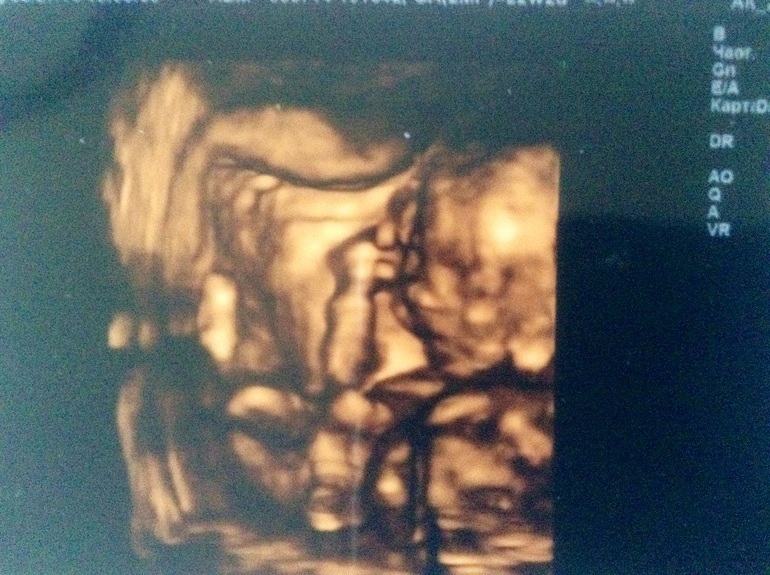

А у нас третья девочка!

УЗИ, КТГ, доплерВстречайте, Варвара Андреевна!

ой, вот это прелесть! поздравляю, дорогая!

принцесса в домике живет!